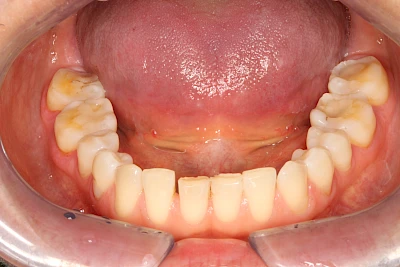

Über die Zeit können verschiedene Prozesse die Zahnhartsubstanzen aufzehren:

- Abnutzung durch Kauen (Abrasion) oder duch durch übermäßiges Knirschen bzw. Pressen (Attrition)

- Säurebedingte Auswaschung (Erosion)

Auswaschung (Erosion) dagegen ist eine Verschleißerscheinung der Zähne aufgrund von immer wiederkehrenden Säureangriffen durch die Nahrung, verstärkt zum Beispiel durch den Genuss säurehaltiger Getränke oder Speisen. Auch bei Menschen mit einer Essstörung (z. B. Bulimie) können die Zähne durch die Magensäure ausgewaschen erscheinen.